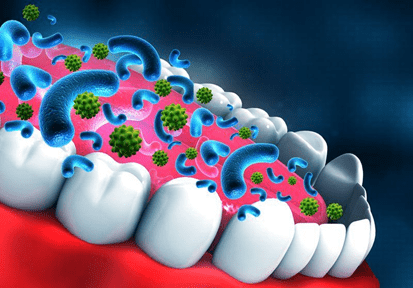

Every time you eat, your teeth are exposed to acids and bacteria. Sugary and starchy foods feed harmful bacteria in the mouth, leading to plaque formation.

Maintaining a balanced diet supports natural saliva production, which protects enamel and washes away food particles.

The Role of Saliva in Protecting Teeth

Saliva acts as a natural defense system. It neutralizes acids, repairs enamel, and reduces bacteria buildup.

Chewing sugar-free gum after meals can stimulate saliva production and protect enamel.